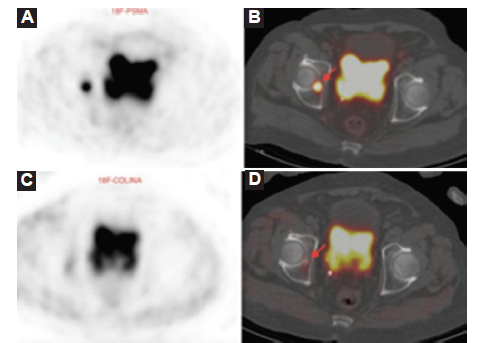

El PSA disparador de la PET/TC mostró una mediana (Q1-Q3) de 3,14 (0,73-8,69) ng/ml. La PET/TC colina mostró una tasa de positividad del 35%, mientras que la PET/TC 18F-PSMA mostró una tasa de positividad del 80%, pero con un PSA disparador ≥ 2 ng/dl la PET/TC 18F-PSMA tuvo un 100% de positivos; mientras que la PET/TC 18F-colina un 55% positivos (Figs. 1, 2 y 3). De las 35 PET/TC 18F-colina negativas, 24 (69%) fueron positivas con PET/TC 18F-PSMA. Todos los PET/TC 18F-colina positivos también fueron positivos con PET/TC 18F-PSMA.